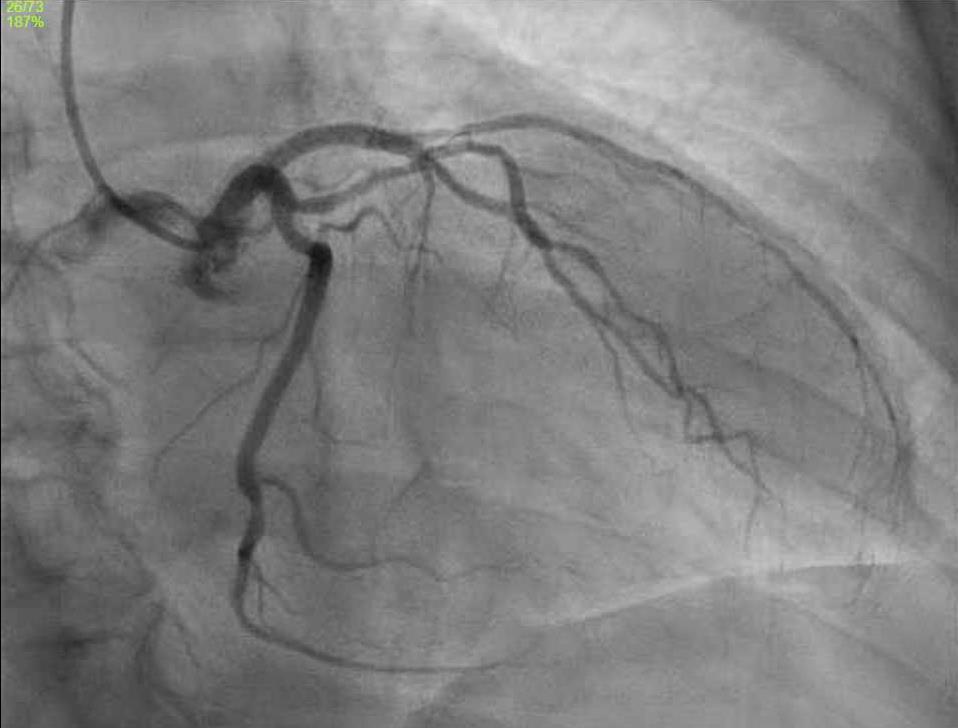

JUNGLE JUICE INDUCED MYOCARDIAL INJURY: CHRONIC USE AND NEW VARIATIONS OF NITRITE PRODUCTS

Matthew Baer1, James Choi1, Vahid Namdarizandi1, Sandra Maria Soler3

1Mount Sinai Morningside-West Hospitals, Icahn School of Medicine at Mount Sinai, New York, NY, United States;

2James J. Peters Department of Veterans Affairs, United States Department of Veteran Affairs, Bronx, NY, United States Presented at the American College of Cardiology (ACC) Annual Meeting that was held in Atlanta, Georgia, United States from April 6-8, 2024.

BACKGROUND/INTRODUCTION: Jungle Juice is an alkyl nitrite derivative commonly purchased at supplement stores and used as an illegal inhalant. Limited case reports highlighting myocardial injury from chronic use have been published, along with recognizing newer variations of illegal nitrites.

CASE PRESENTATION: A 60-year-old male with hyperlipidemia presented after a syncopal episode. He presented multiple times prior for syncope, which was attributed to chronic, daily use of a nitrite supplement, Jungle Juice, and was treated with methylene blue each time. He now admitted to taking a different brand of Jungle Juice. Troponin 1300, blood pressure 195/91, and EKG unremarkable, with myocardial injury attributed to demand ischemia from rebound sympathetic response and coronary vasospasm from chronic Jungle Juice use. No percutaneous intervention was attempted, as he denied chest pain and was asymptomatic when seen by Cardiology. Myocardial perfusion scan showed minimal apical and anterolateral ischemia with reversible hypoperfusion; ejection fraction of 68%. Chronic and potentially lethal doses of nitrites from inhalants may lead to coronary artery vasospasm with increased sympathetic tone similar to the reaction seen with rebound angina from chronic nitrate tolerance. Although nitrite use usually presents with hypotension and syncope due to methemoglobinemia (current literature highlights cases after single episode use), this patient experienced rebound sympathetic response immediately after presentation leading to myocardial injury. This may be due to his daily use, leading to “withdrawal” and a depletion of nitric oxide availability. Further use by this patient and recurrent episodes of cessation, will likely lead to more myocardial demand ischemia and possible cardiac arrest. Newer variations in nitrites also contain more potent concentrations and novel compounds, with patients presenting “non-traditionally” after use.

CONCLUSION: Jungle Juice contains derivatives of nitrite inhalants that are becoming increasingly diverse in supplement stores. It is important to identify the frequency and type of use in patients to properly identify symptoms and order further cardiac workup.